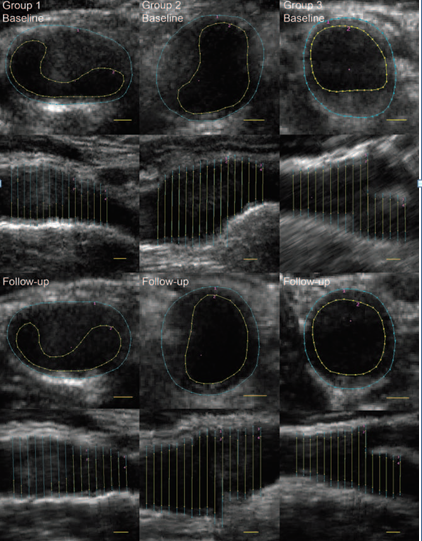

Similarly, diet-related metabolites such as L-Lysine and L-Carnitine are also associated with reduced cIMT [147]. Another randomized control trial of a two-year follow-up indicated a significant 5% reduction in the carotid vessel wall volume (VWV) and –1.1% change in the cIMT from baseline with dietary weight-loss strategies such as following low-fat, Mediterranean, or low-carbohydrate diets [156]. Fig. 7 (Ref. [156]) depicts the changes in the vessel wall volume of the common carotid artery at baseline and follow-up for the population consuming a low-fat diet (Group 1), the Mediterranean diet (Group 2), and low-carbohydrate diet (Group 3). Besides all this, the adoption of Western diet plans is associated with increased cIMT in the common carotid artery and leads to adverse vascular events [149]. A recent study indicated that patients with ischemic stroke, especially with carotid atherosclerosis, have a high intake of saturated fatty acids and low consumption of fruits, vegetables, and unsaturated fat nutrients [157].